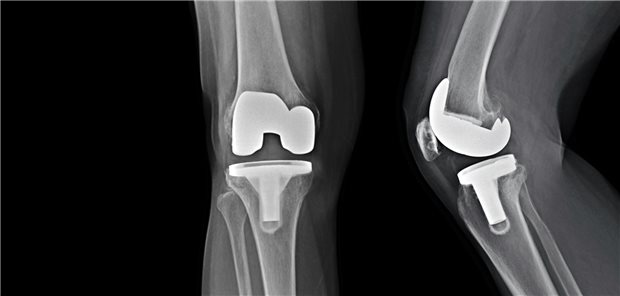

Damit ein Gelenkersatz nachhaltig gelingt, ist rund um den Eingriff einiges zu beachten. Dem widmet sich in der neuen Gonarthrose-Leitlinie, vor allem das neue Kapitel „Allgemeine Knieendoprothetik“. Die wichtigsten Infos im Überblick.

Die neue Gonarthrose-Leitlinie ist da: Es gehe vor allem darum, unnötige Operationen zu vermeiden zugunsten der wirksamen konservativen Therapien, so Leitlinien-Koordinator Johannes Stöve im Gespräch mit der Ärzte Zeitung.

Regelmäßige Bewegung und individuell angepasste Physiotherapie mit Kraft-, Ausdauer- und Mobilitätstraining zählen bei Gonarthrose mehr als alles andere: Sie bleiben das Fundament der Behandlung.